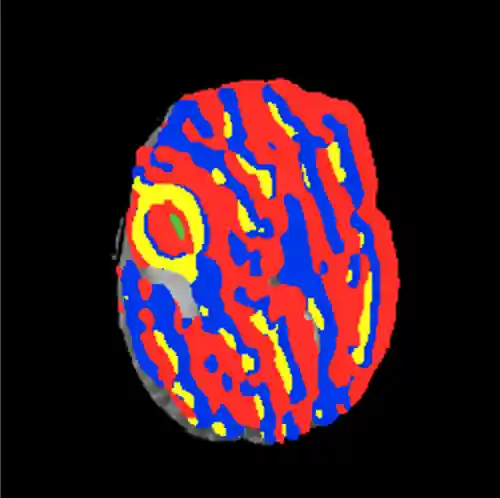

I tried out several different methods for sampling patches, which had a large impact on the results. I began randomly selecting patches of a given class from the data and repeating this for all five classes. However, with this sampling method approximately half of the background patches were just the zero-intensity area with no brain, so the model classified most patches with brain tissue as tumor, and only the black areas as background (Figure 9).

Figure 9: (Left) results of segmentation without excluding exclusively zero-intensity patches. Notice that even healthy tissue is classified as tumor. (Right) results of segmentation after restricting the amount of zero-intensity pixels allowed in a given patch. The tumor prediction is now restricted mostly to the actual area of the lesionI then restricted the selection process to exclude patches in which more than 25% of the pixels were of zero-intensity. This greatly improved the results, one of which can be seen on the right in Figure 9.